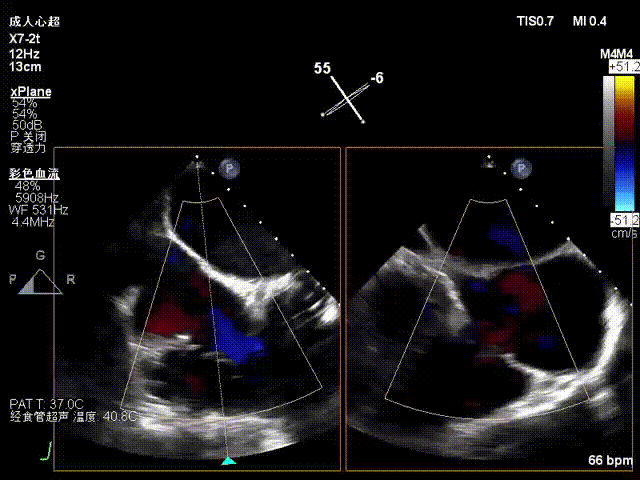

食管中段RV inflow-outflow引导前叶及隔叶分别捕获

术后超声显示反流基本消失